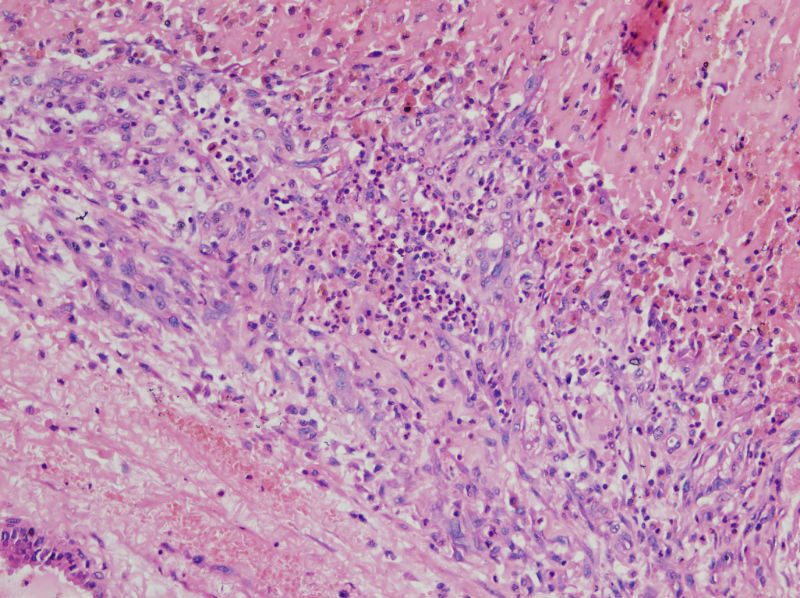

男,44,甲状腺囊肿.直径1.5公分,内流清亮液

请教老师们:有上皮内衬的一侧为囊壁的内衬上皮,是滤泡上皮吗?肉芽组织及出血区应该是继发的反应吧?

结节性甲状腺肿伴出血、囊性变。囊肿边上的滤泡大小不一,纤维组织增生,还可见炎细胞浸润。